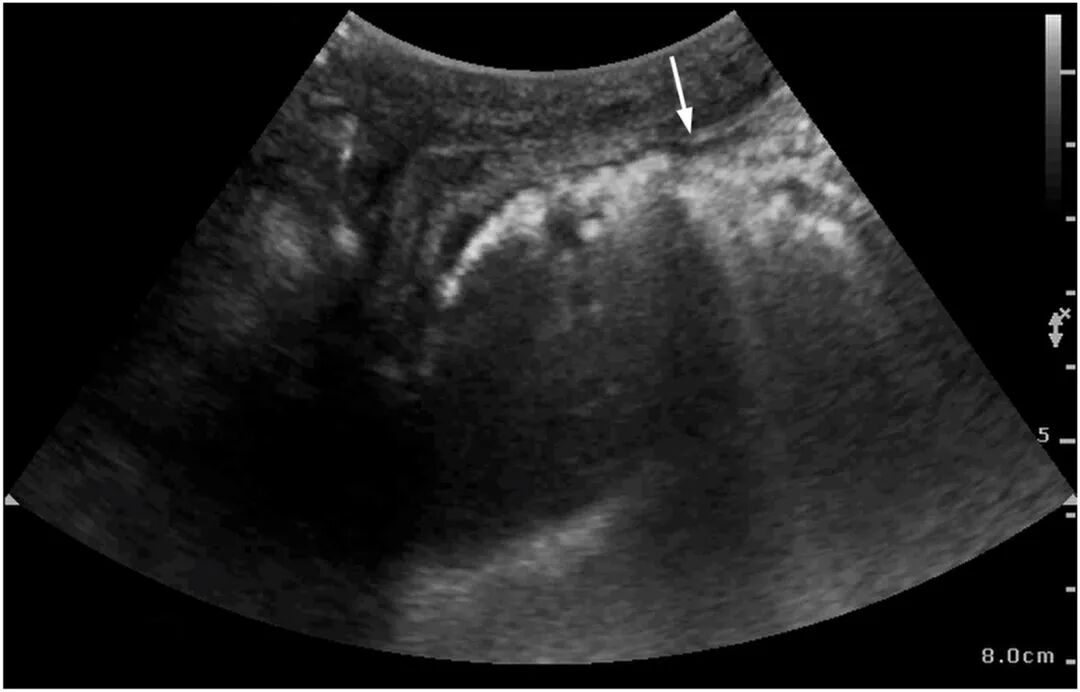

图2 床旁超声剑突下切面显示胃壁"彗星尾"伪影

图3 床旁超声左肋间切面显示胃壁"彗星尾"伪影(箭头)